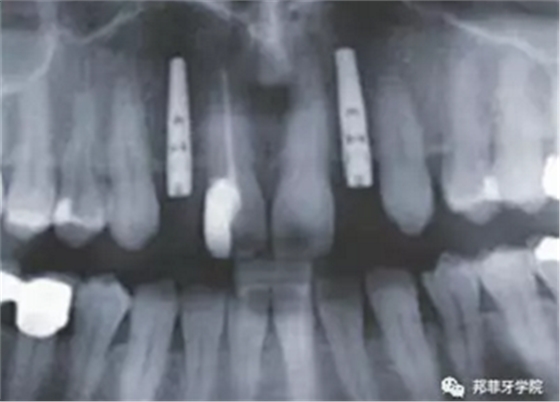

圖2:治療前全景片

圖 10:拍片復(fù)查植體位置